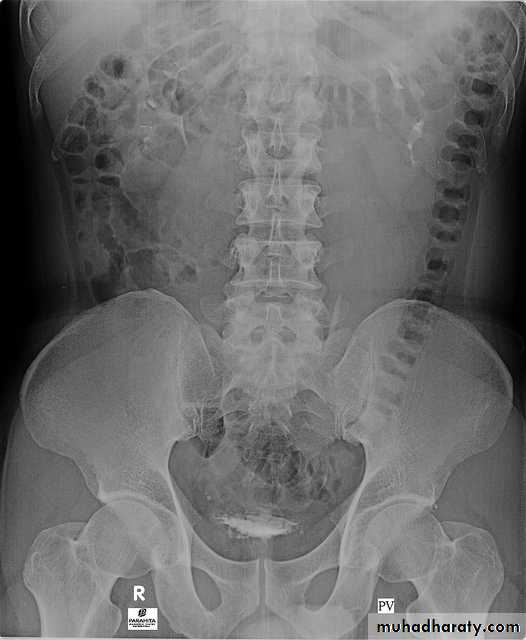

A. First a plain x-ray of the abdomen is taken before the injection of the contrast media, also known as A KUB (kidney, Ureter and Bladder). Calcification & stones may be obscured & missed by contrast media if plain film not takenfirst .B. Films taken after injection of contrast’ medium: